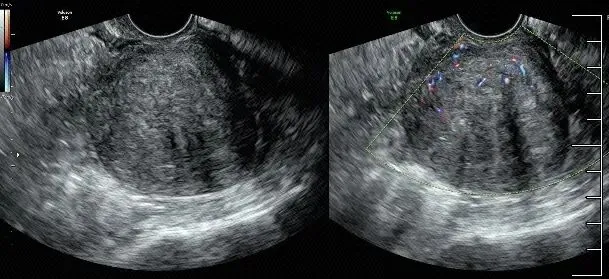

子宫腺肌症

●子宫腺肌病好发于已生育、多产或有多次宫腔操作史的妇女,少数也可发生在年轻、无婚育及宫腔操作史的女性,它是由于具有功能的子宫内膜腺体细胞及间质细胞向肌层内侵蚀而产生的病变,伴随着子宫平滑肌细胞的增生。

子宫腺肌病典型超声特征示意图

不对称增厚(A)、囊肿(B)、高回声岛(C)、扇形阴影(D)、子宫内膜线下的线状和芽状高回声(E)、病灶内横贯的血管(F)、不规则连接区(G)和连接区中断(H)。

局灶性子宫腺肌病,边界不清,未见明显包膜,内部血供增多。